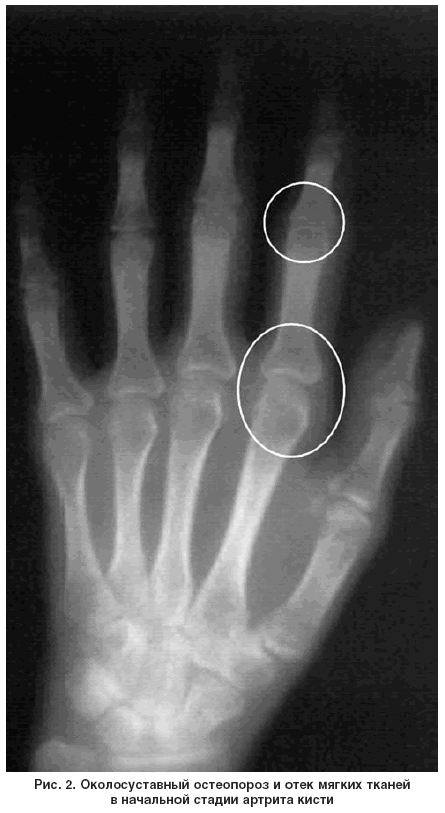

Рентгенологические признаки артрита на ранней стадии:

околосуставный остеопороз (основной признак), периартикулярный отек мягких тканей, возможно расширение суставной щели (в мелких суставах) (рис. 2).